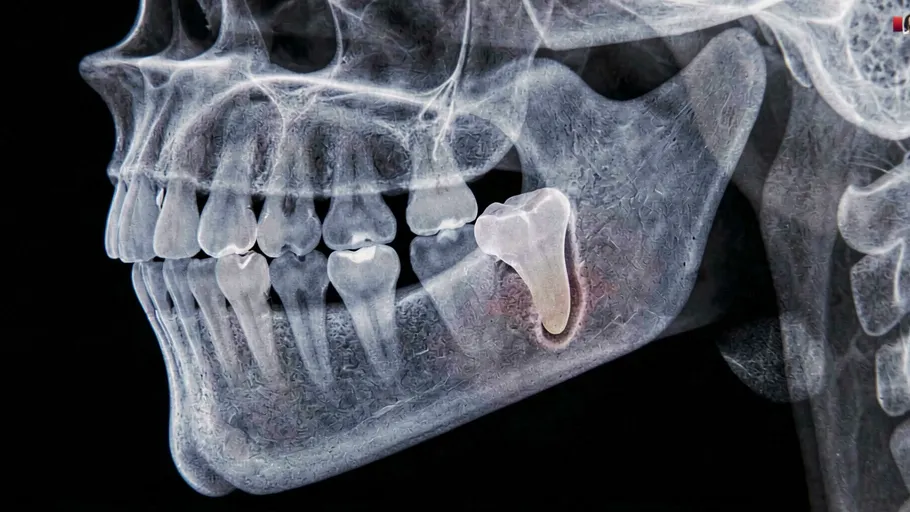

- Подготовка: Перед процедурой врач проводит обследование и может выполнять рентгенографию для более детального изучения положения зуба мудрости. По результатам анализа определяется, каким способом будет производиться удаление.

- Ультразвуковая технология: Ультразвуковая техника используется для разрезания и размягчения тканей вокруг зуба мудрости, что делает его более доступным для удаления.